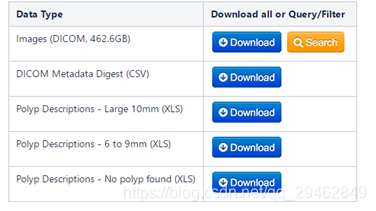

五、结肠癌CT数据

数据下载链接:https://wiki.cancerimagingarchive.net/display/Public/CT+COLONOGRAPHY#dc149b9170f54aa29e88f1119e25ba3e

数据介绍:CT扫描诊断结肠癌。 包括没有息肉,6-9mm息肉和大于10mm息肉的患者的数据。 该系列中有825例带有XLS片的病例,提供了息肉描述及其在结肠段中的位置。